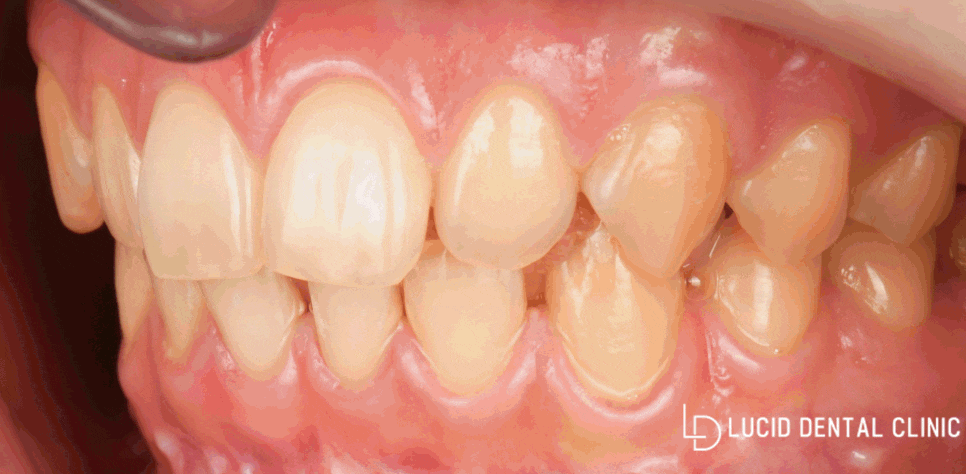

어떤가요?

interdental gap이 없어지고,

변색도 해결된 모습입니다.

전후로 봐도

드라마틱한 변화를 느낄 수 있는데요.

지금 보여드린 증례가

단 하루 만에 끝난 치료라면 믿으시겠습니다.

당일 치료 맞습니다.